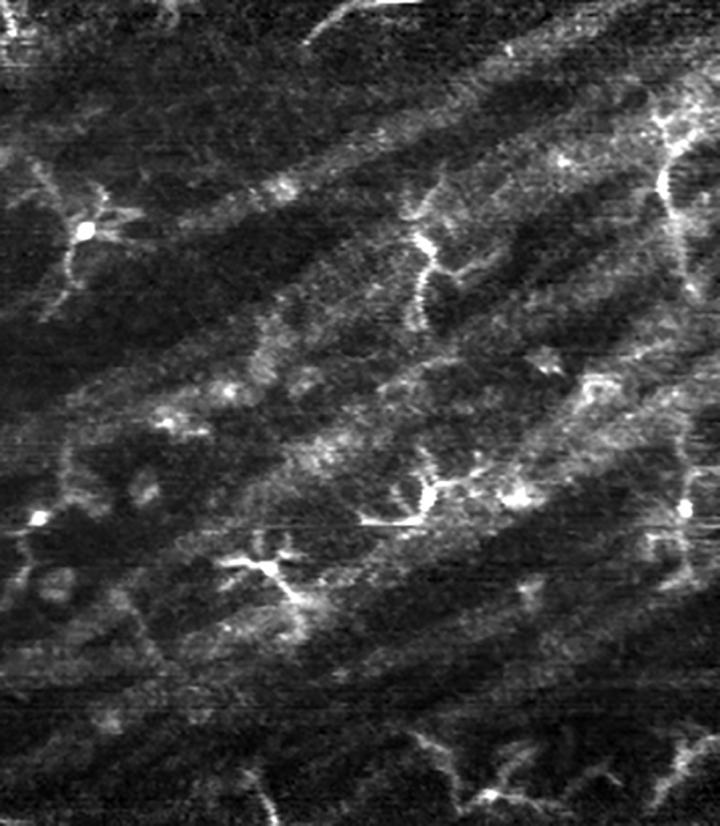

A label-free imaging technique can illuminate the characteristics of immune cells called macrophages in the eyes of healthy humans and patients with glaucoma, according to a study. Macrophage cells in the retina have typically been examined using labeling techniques and animal models. As a result, little is known about the density, distribution, and movements of these immune cells in the eyes of living humans of various ages, in both healthy and diseased states. Daniel Hammer, Zhuolin Liu, and colleagues used a high-resolution, label-free imaging technique called adaptive optics optical coherence tomography in 15 healthy individuals and four patients with glaucoma, a group of eye diseases that can cause blindness. Cell density decreased with age in healthy participants, by approximately 2% per year between the ages of 20 and 70 years. In patients, cell density was higher on the defective side of the retina, compared with the normal side. Moreover, cell processes moved more quickly and covered a smaller area of the retina in patients compared with healthy participants. The findings suggest that macrophages play a role in the progression of glaucoma, possibly migrating to active areas of disease during early stages. According to the authors, the findings provide a label-free technique to examine retinal macrophages in live human eyes and point to potential biomarkers that could facilitate the development of treatments for glaucoma and other age-related ocular and neurological diseases.

Article #20-10943: "Label-free adaptive optics imaging of human retinal macrophage distribution and dynamics," by Daniel X. Hammer, Anant Agrawal, Ricardo Villanueva, Osamah Saeedi, and Zhuolin Liu.